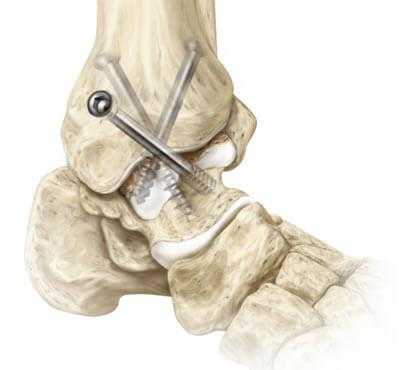

В данном случае применяются все виды оперативного лечения, но наиболее актуален внутрисуставной метод. Популярен артродез голеностопного сустава пластиной, при котором облегчается установка угла между большеберцовой костью и голенью.

- Разрез мягких тканей оптимален на передней или внутренней поверхности сустава;

- Получив доступ к хрящевым поверхностям - они удаляются вместе с поражёнными элементами костной ткани;

- Между костями располагаются трансплантаты, которые прочно фиксируются;

- Между голенью и стопой формируют угол 90°;

- Накладываются швы и гипсовая повязка.

В гипсе придётся проходить 6-9 месяцев в зависимости от рекомендаций врача, затем назначается курс лечебной гимнастики для частичной иммобилизации оперированной конечности. Артродез голеностопного сустава обеспечивает полную его неподвижность на всю жизнь.